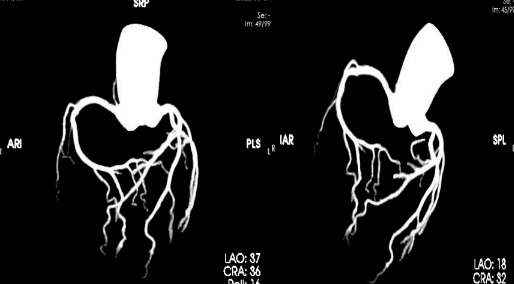

我院放射科通过 CT 联影 UCT-710

成功开展

首例冠脉动脉 CT 血管造影(CTA)检查

填补了我院在此项技术的空白

此种方法是将造影剂通过静脉途径以 4-6ml/s 的速度输入患者体内,利用人工智能、软件智能跟踪及心电门控等技术,对冠状动脉及其分支,心脏室壁运动等进行清晰显示。与传统冠脉造影相比,冠脉 CTA 对于冠脉开口变异,能更好地显示血管的开口情况,更好地确定冠脉斑块的性质, 并能显示冠脉以外的病变:如心肌桥、肿瘤等,对心脏和大血管解剖结构的显示优良。